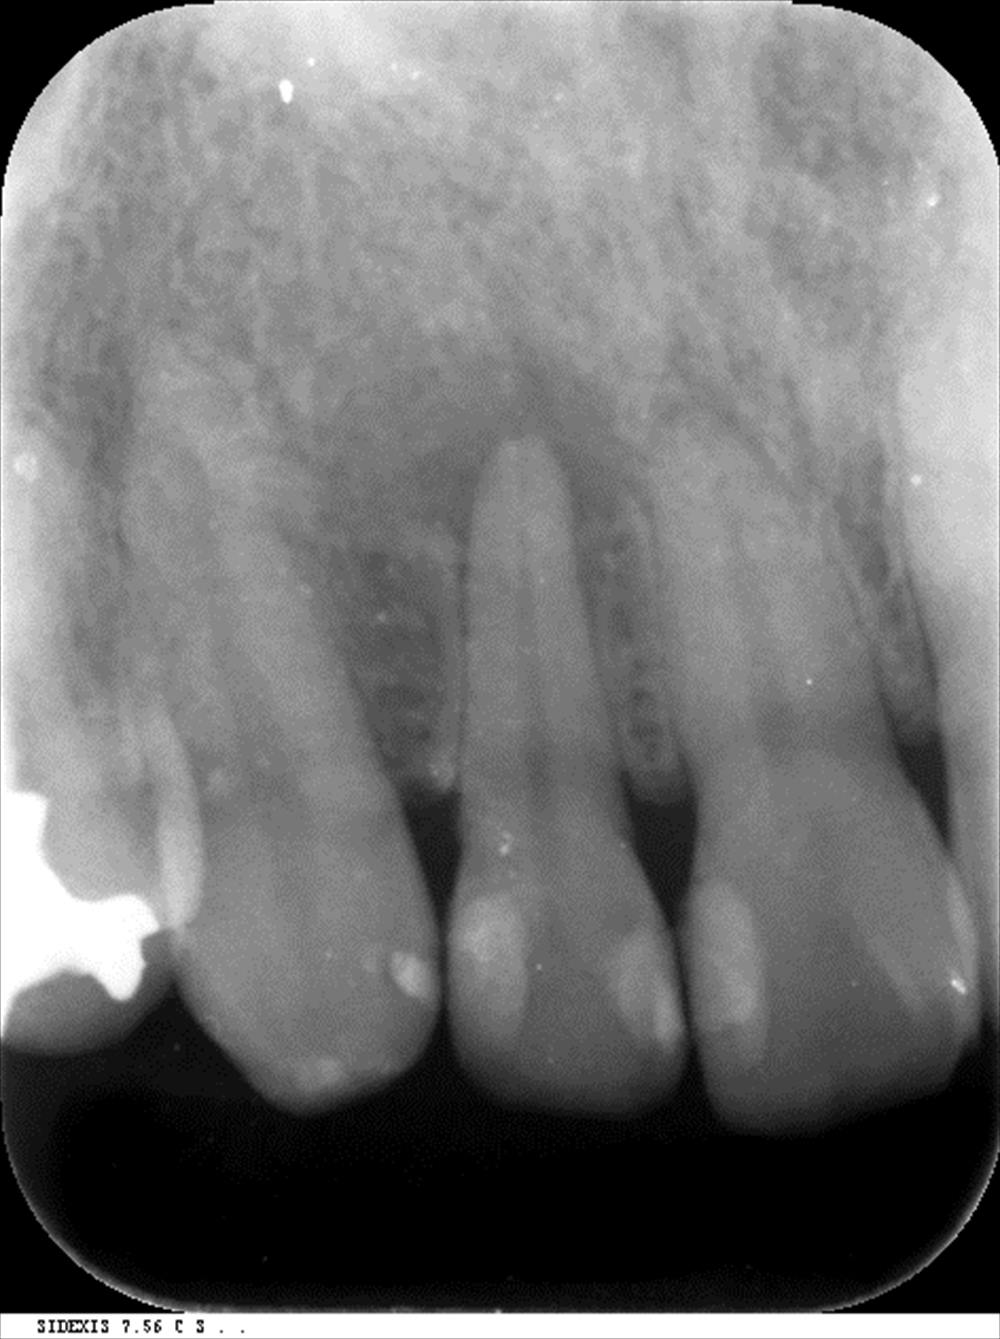

こんにちは。院長の武川です。メンテナンス中に発覚!

右上2番神経死んでる。。。